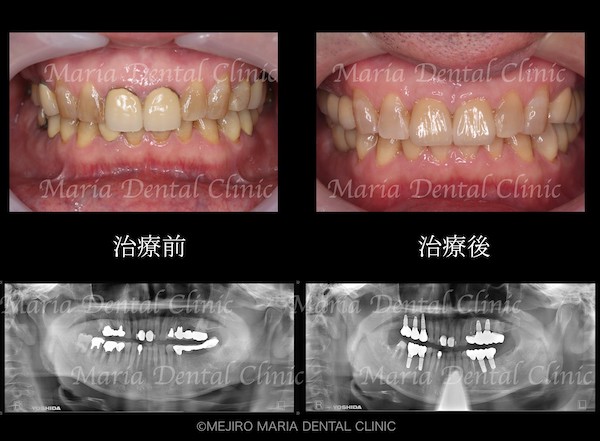

治療前の状態・主訴

患者様は、長年にわたり臼歯部(奥歯)の噛み合わせの調子が悪いことと、食事の際に痛みを感じることを主訴に来院されました。前歯部から口腔内を確認すると大きなトラブルは確認できませんが、レントゲン撮影と口腔内診査を行うと、多数の臼歯部の歯牙(歯)が歯根破折により抜歯を余儀なくされる状況でした。

今回の症例では、歯根破折していた5本の歯牙(下の写真・赤矢印)に対して、抜歯を提案した。また、診断用WaxUp(ワックスアップ)を行ったところ左下のブリッジ(青丸)と右下(青矢印)の噛み合わせ平面が乱れており、咬合に負担をかけていることが予想されました。そのため、最終的にそれらの不調和を改善し、適切な噛み合わせにすることをゴールとして治療を開始しました。

治療後の様子

最終段階に入る前に、仮歯の状態で咬合の安定が確認できたことから、最終補綴処置を行いました。最終補綴処置後の経過は良好で、今後はメンテナンスをしながらインプラントを含めた根尖周囲組織、補綴物(被せ物)の長期的な経過を確認していきます。

今回の症例は、臼歯部の崩壊により前歯部に負荷がかかり始め「咬合の崩壊」の手前の状態でした。患者様も、徐々に歯が悪くなっていくことを十数年もの間、恐怖に感じていたものの、歯科医院の受診からは遠ざかっていたようです。初診時に「最近では食事することもつらい」と訴えていたことから、患者様のQOL(生活の質)は著しく低下していたことが予想されました。この状況をできる限り早く、確実に改善することが求められる症例でした。

治療期間は2年間と比較的長くなりましたが、初診時の段階で確実な診査、診断を行うことで、治療中のトラブル(仮歯の脱離、痛みなど)を最小限に抑え、各分野の専門医が最短で最良の処置を施すことで、スムーズな治療が実現できました。